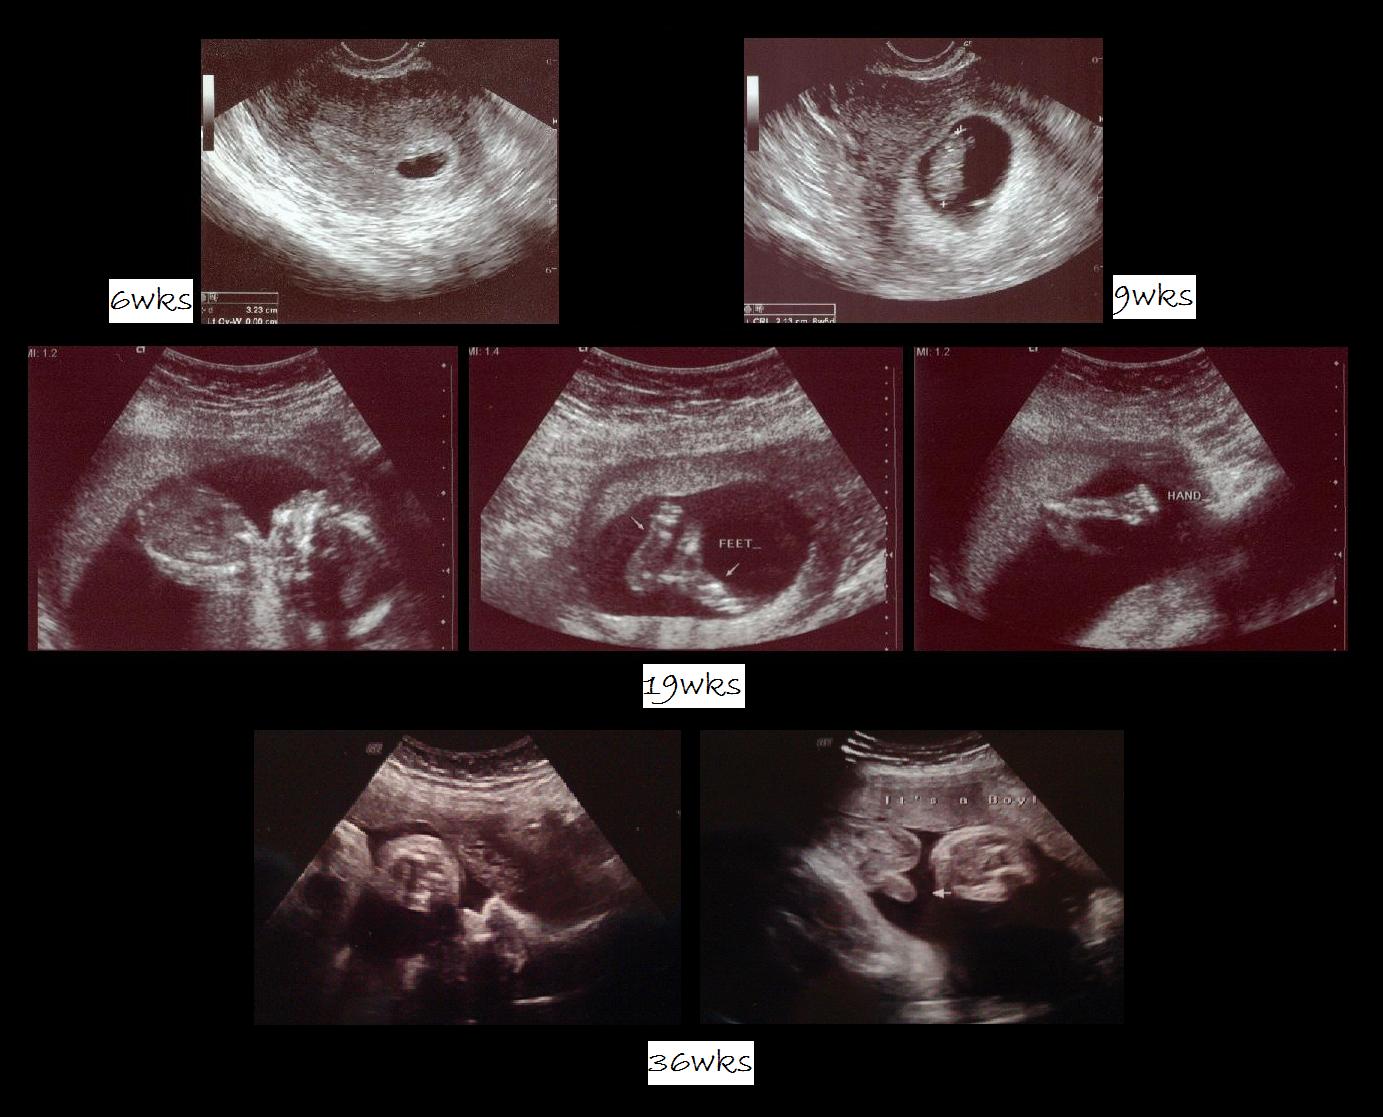

Ultrasound - I first found out I was pregnant with the simple home test.  It was important for me to confirm this surprise with the Doctor.  So when we had our first ultrasound it was a mixture of emotions.  I think Hubby and I both held our breaths.  And then once we saw the sack on the screen the Doctor gave us the confirmation and finally came the excitement.  Hubby actually told me he heard me release the breath I was holding.  Below are some of the pictures over the months, when my turtle was growing in my belly.  :)